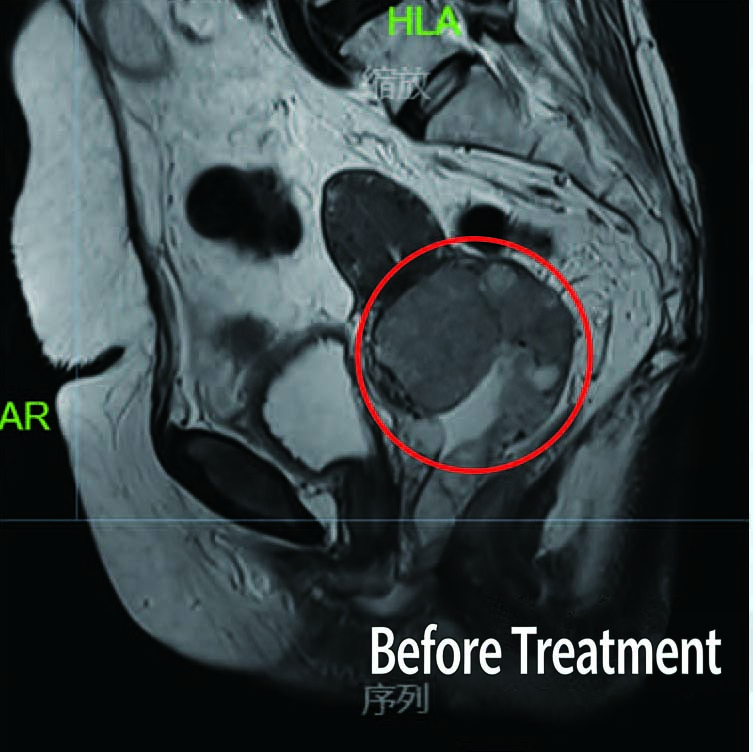

Before Treatment

Patient: 53-year-old female

Diagnosis: Diagnosed Stage 111B Cervical Cancer in February 2020

Treatment History: Patient underwent chemotherapy at another hospital with unsatisfactory results.

Treatment at Our Hospital: Definitive radiotherapy for cervical cancer (External beam radiotherapy+ brachytherapy)

Outcome: Significant reduction in the size of the tumor observed post-treatment, with complete disappearance of the large tumor.